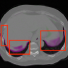

Figure 3: Visual validation of proposed Conv2warp method without (λ=0𝜆0\lambda=0 ) and with regularization (λ=0.001𝜆0.001\lambda=0.001 ) in our loss function on POPI dataset. Overlay images represents source or warped images in magenta and target image in green. Red rectangles in overlay images with Is(x+u)superscript𝐼𝑠xu{I}^{s}(\textbf{x}+\textbf{u}) show unrestricted flow of pixels when no regularization is used. Smoother deformation fields are obtained with regularized Conv2warp. Brighter pixels in magnitude images on left represent large displacements.

In Fig. 3 Conv2Warp without (λ=0𝜆0\lambda=0) regularization and with (λ=0.001𝜆0.001\lambda=0.001) regularization are shown in 4th and 5th columns respectively and their corresponding DVF magnitudes in 6th and 7th columns, respectively. It can be observed that the unconstrained loss function results in some unrealistic deformations (red rectangular regions in 4th column) while a more realistic deformations are visible for the constrained loss proposed in Conv2Warp (5th column). A smooth deformation can be seen in the magnitude image of the DVF uregdelimited-∣∣subscriptu𝑟𝑒𝑔\mid\textbf{u}_{reg}\mid (7th column). Colour overlay images show a large improvement in the alignment of source images Issuperscript𝐼𝑠I^{s} with the target images Itsuperscript𝐼𝑡I^{t} (3rd column) with Conv2Warp method (5th column). Fig. 4 shows the results on T1 MRI test datasets which were first rigidly aligned to MNIspace and then co-registered using Conv2Warp. It can be observed that Conv2Warp handles different magnitudes of non-linear deformations.